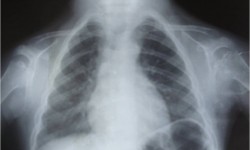

Asphyxiating Thoracic Dystrophy (Jeune Syndrome)

By Admin | September 30, 2013 - 12:37 pm | Musculoskeletal, Skeletal Dysplasias

Fig.1-Chest P.A

Fig.2 -Chest-Lateral